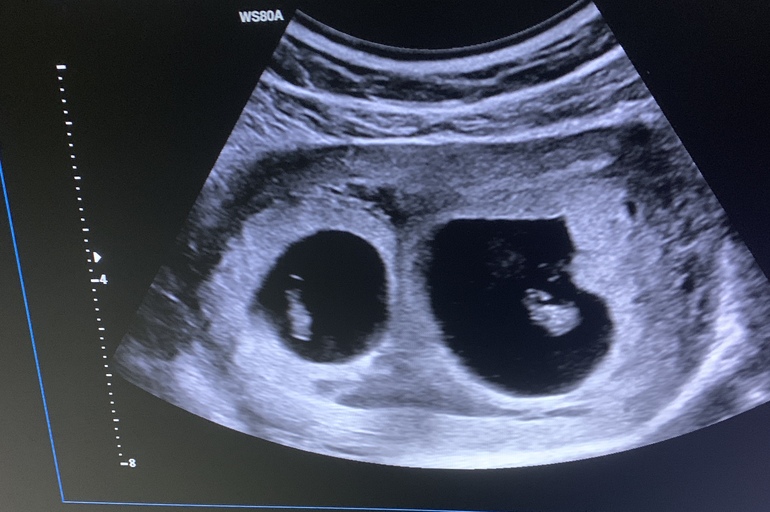

А если многоплолная беременность, а физиология матки? Ведь не все женщины имеют правильное расположение матки, у многих загибы в ту или иную сторону

Матка тут вообще не при чем, пя может быть в любой части матки, справа, слева, сверху-справа, снизу-слева и т.д. Да хоть трижды винтом, а положение хориона относительно эмбриона будет определённым. И смотрят это до 8 недель пока хорион хорошо виден и эмбрион макстмально близко к хориону.

Если УЗИ транс вагинальное, то слева мальчик, справа девочка. На этих снимках девочка.

НЮША (ник в ИГ Visla79), у меня тоже справа, девочка? 🤭

Снимок не самого лучшего качества, очень плохо видно хорион. Но чуть больше на жевочку

Слева мальчик, справа девочка. Узи трансвагинальное. По снимку автора девочка выходит)